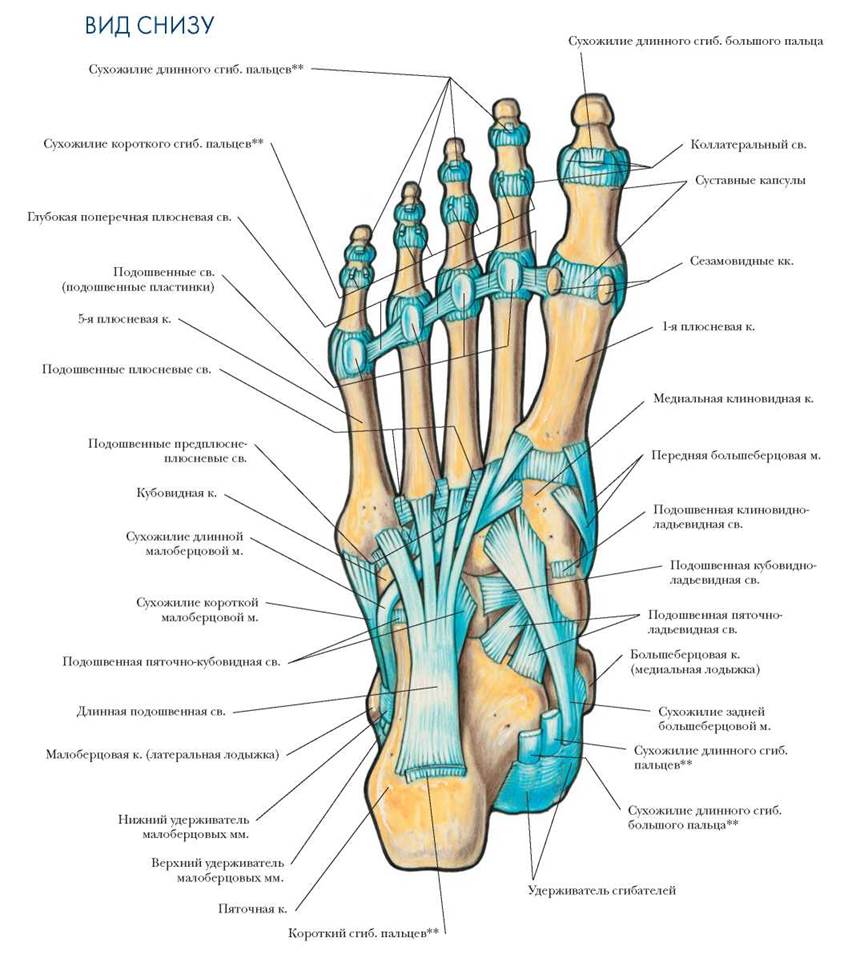

Анатомия голеностопа: Сухожилия и их строение